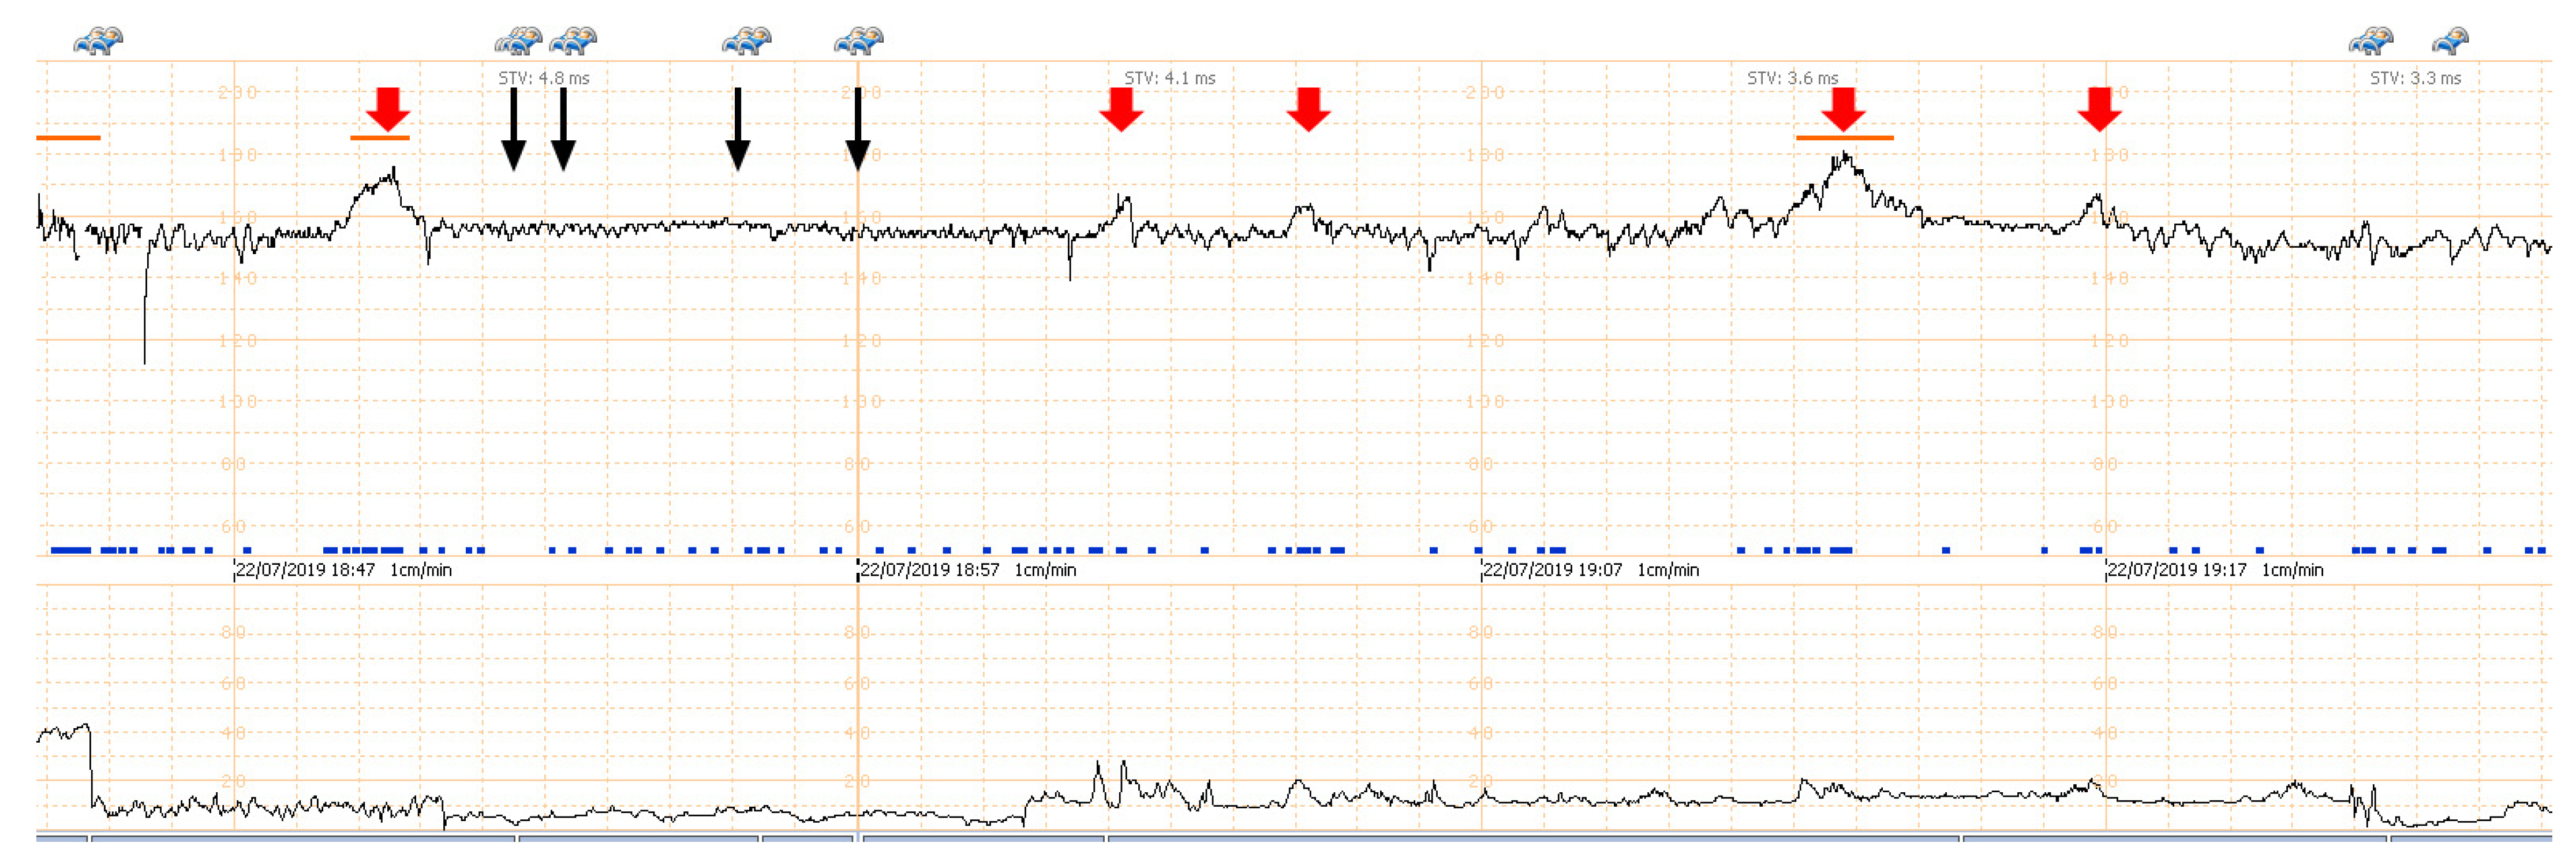

A 32-year-old pregnant woman, G4 P2102, attended her first visit of antenatal care at 23+3 weeks of gestation. Ultrasound examination for anomaly screening demonstrated cardiac defects, including double-outlet right ventricle: DORV-TOF type, with severe pulmonary stenosis (Figure 1) and left superior vena cava. Detailed ultrasound showed no associated abnormalities. Fetal biometry was consistent with gestational age except abdominal circumference and estimated fetal weight, which were relatively low (at 10th percentile), reflecting some degree of growth restriction. However, detailed ultrasound on the follow-up scans at 28 weeks of gestation showed subtle abnormalities, including malrotation of both kidneys, the hilum or renal pelvis facing posteriorly to the abdominal wall (Figure 2). Furthermore, 3D-ultrasound revealed abnormal external ear structure (markedly prominent crus of anti-helix) (Figure 3). Non-stress tests (NST) showed spontaneous fetal heart rate (FHR) accelerations (normal reactive tests) (23+3 weeks). Interestingly, the fetus showed persistent non-response to acoustic stimulation tests at 26, 30, 32, 36 and 38 weeks (no FHR accelerations as well as no quickening perceived by ultrasound) (Figure 4), probably reflective of auditory dysfunction. Based on the findings of heart defect, ear defect, renal defect and growth restriction, several differential diagnoses were listed, including CHARGE syndrome. Theoretically, fetal blood sampling for molecular genetic tests should be performed. Nevertheless, since no lethal condition was identified and the couple wanted to continue pregnancy regardless of investigation results, prenatal invasive diagnosis was avoided, and we waited for postnatal work-up instead. She had no significant underlying disease and no familial history of hereditary diseases. Her pregnancy was uneventful except that she developed gestational diabetes (GDM) at 28 weeks of gestation, which was well-controlled with diabetic diet.

Figure 4.

Non-stress test/acoustic stimulation: the fetus at 34 weeks of gestation shows spontaneous fetal heart rate (FHR) acceleration (thick red arrow); but no response to acoustic stimulation (thin black arrow).

Ear structural abnormality in our case was first subjectively diagnosed, but it seems to be more significant when combined with its function. As already known, fetuses are very sensitive to acoustic stimulation, routinely used in antenatal surveillance, leading to FHR accelerations and fetal quickening. We took advantage of this stimulation to test the auditory perception. Because the fetus persistently showed no response to acoustic stimulation, either by FHR acceleration or quickening in spite of having spontaneous FHR acceleration and quickening, it may reasonably be concluded that the fetus was likely to have auditory dysfunction, probably associated with structural abnormality of the ear canal and external ear abnormality, as seen on 3D-ultrasound.